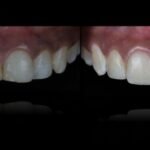

Punto Bajío Casos Clínicos Prótesis Fija sobre Implante unitario Inicio Provisional Final Prótesis Parcial Fija sobre 2 Implantes 2 Implantes Final Prótesis Bucal Removible Inicial Inicial Superior Inicial Inferior Rayos X Inicial Rayos X Inicial Frontal Final Final Superior Final Inferior Prótesis Parcial Fija/ Coronas de Circonio Sonrisa Inicial Foto Inicial Foto Inicial Inferior Foto Final Inferior Foto Final Sonrisa Final Prótesis Total Protesis Inmediatas 1 Protesis Inmediatas 2 Prótesis Removible/ Coronas Metal-Ceramica Carillas Incrustaciones Endodoncia